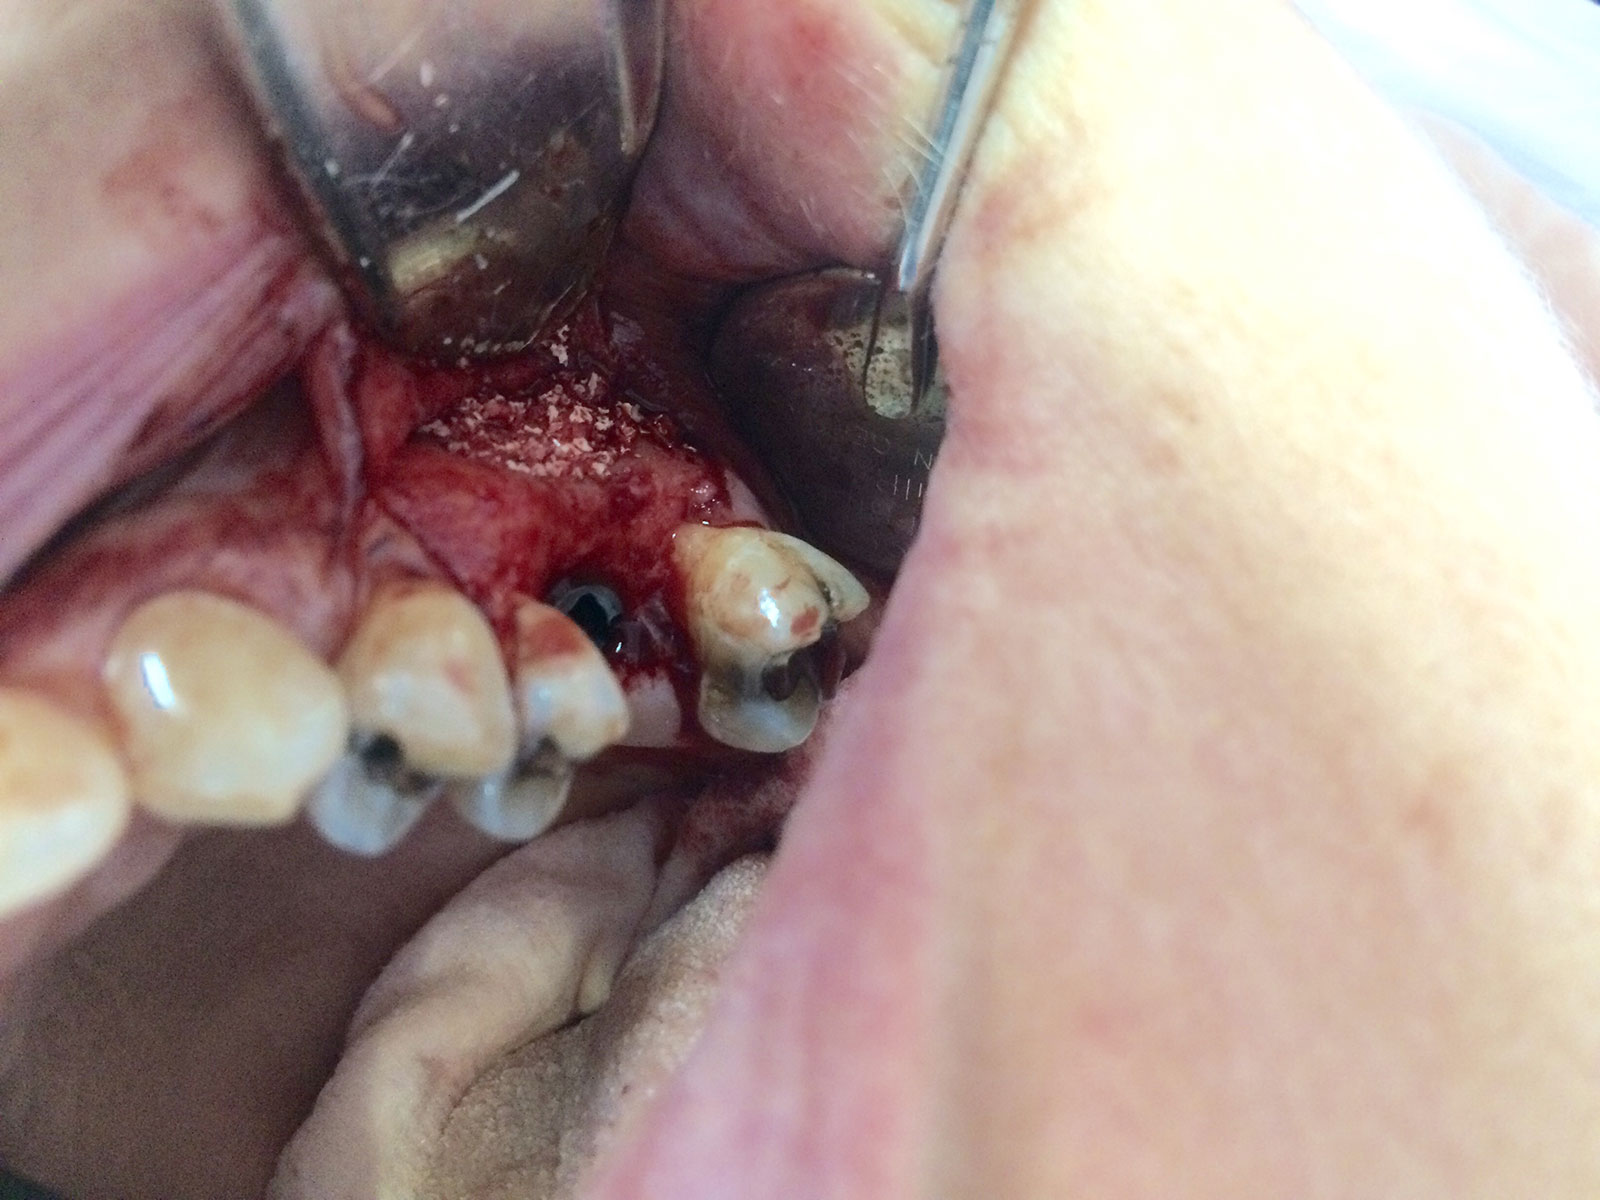

Sinus Grafting Procedures

A sinus grafting procedure, also known as a sinus augmentation, is for patients who have insufficient natural bone in the areas where dental implants are needed. They are long lasting, strong and sturdy, and fit and function like natural teeth. The procedure involves adding bone, either your own natural bone from another part of the body, from a donor or made of processed or synthetic bone material, and placing it below the sinus so that the implants can be placed. After the bone has healed and developed, usually around four to 12 months, the dental implants can be placed.

The photos on this website are from real surgeries performed by Dr. Ulloa. Due to the

graphic nature of the images and content, viewer discretion is advised.

Click to enlarge images